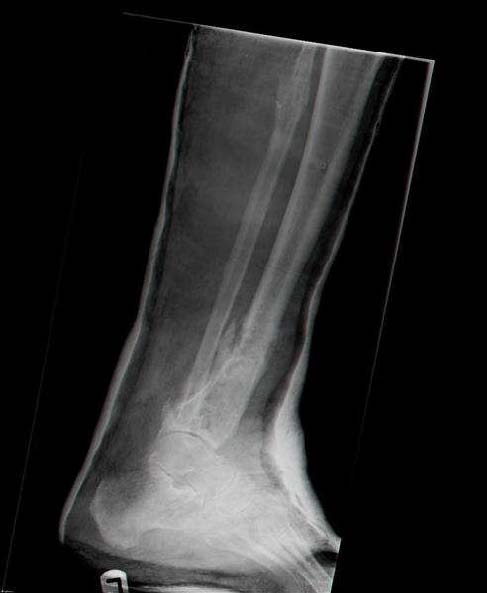

Male 54 years old, diabetic, blind in both eyes, with infected (MRSA) non union distal tibia after fracture 8 month ago. In acute phase treated by ORIF with LCP tibia and fibula. Treatment complicated by infection and after 6 month hardware was removed and treatment continued by cast fixation. You can see malposition of fragments In this stage beginning treated by Ilizarov fixation with use Hexapod system, allows anatomical position of fragments and you see signs of union.

Sorry, I wiil tray now pictures of my case.